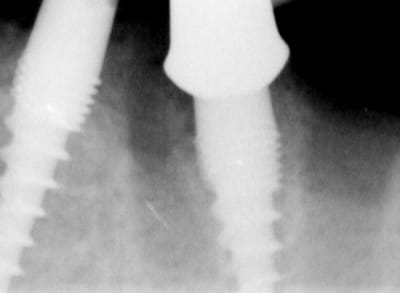

attention exces de ciment distal 36....

Il semblerait que ces excès causerait d'emblé des péri-implantites selopn les paro.

> attention exces de ciment distal 36....

> Il semblerait que ces excès causerait d'emblé des péri-implantites selopn les

Bonjour flicflac,

Oui ca semble ....sur la opg radio tu peux voir la situation seulement deux semaines après l´implantation immédiate 34 jusqu´à 36 et 45, les derniers 2 photos montrent la même situation après un an ( où on a enlevé la supra construction pour un contrôle). Sur ce cas je voulais montrer la bonne régénération osseuse et de la gencive.